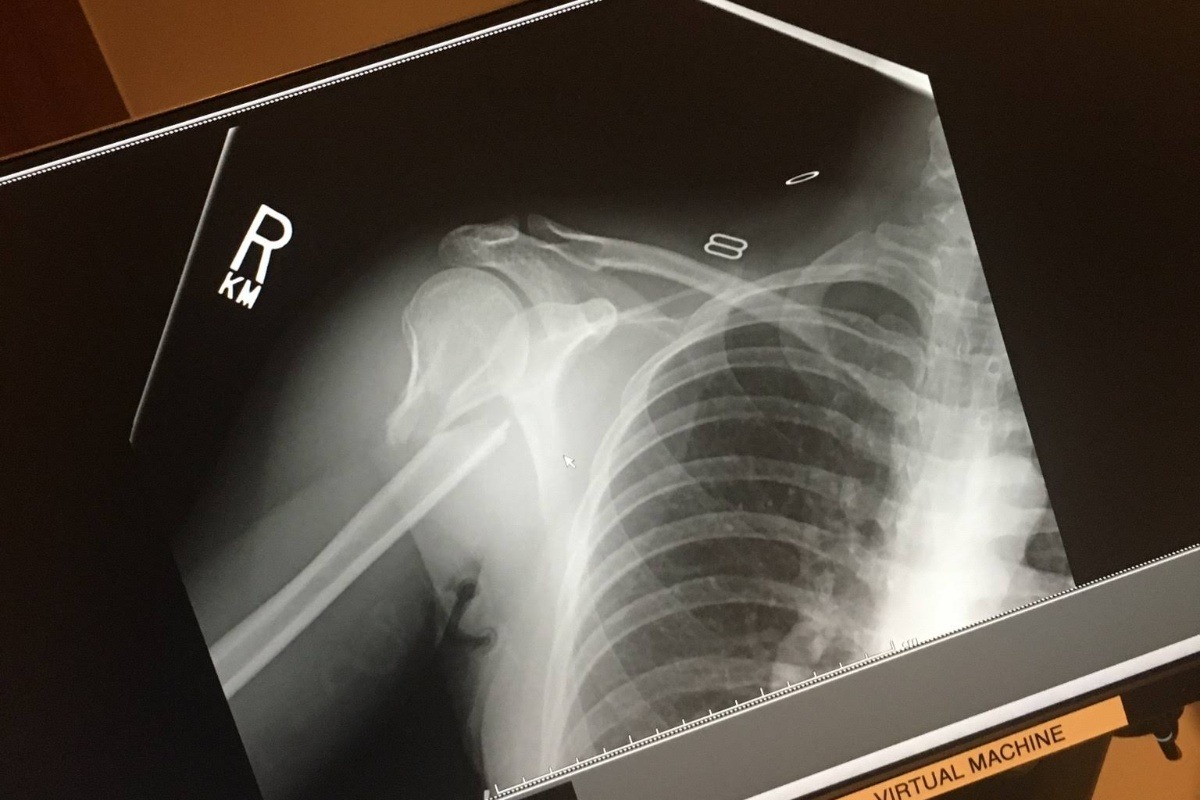

Valerie does not know we are doing this. In December, Valerie broke her humerous in a snow boarding accident. She had 10 screws and a plate to hold it all back together. It got infected, she had to have three additional surgeries. It has now been over 6 months of medical treatments, surgeries, suffering and bills. If you can help, we will appreciate it.